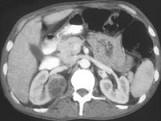

问题 男,35岁,右侧腰部疼痛伴发热,请根据所示图像,选择最可能诊断 ( )

选项 A.右侧肾脓肿 B.右侧单纯性肾囊肿 C.右侧囊性肾癌 D.右肾转移瘤 E.前列腺脓肿

答案 AE